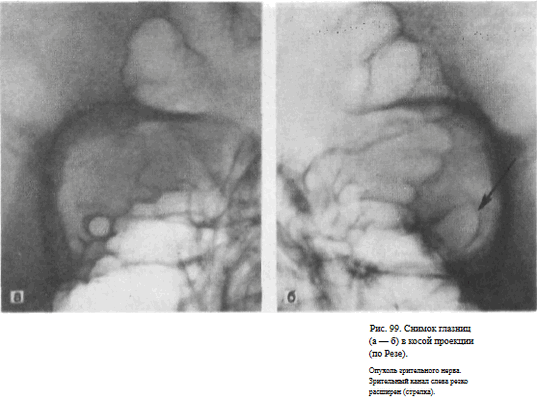

Информативность снимка. На снимке отображается зрительный канал, имеющий обычно неправильно-округлую форму с четкими резкими контурами. Видны также вход в глазницу, решетчатые ячейки (рис. 98, а, б). Расширение зрительного канала, возникающее при опухолях зрительного нерва, как правило, может быть достоверно выявлено только путем сравнительного анализа снимков правой и левой глазницы (рис. 99, а, б). Поэтому снимки глазниц в косой проекции по Резе всегда следует производить с обеих сторон.

Изображение зрительного канала при правильной укладке проецируется вблизи наружной стенки глазницы в виде четкой кольцевидной тени.